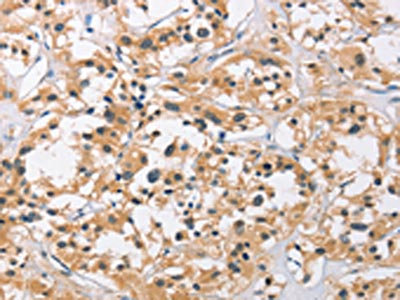

The image on the left is immunohistochemistry of paraffin-embedded Human thyroid cancer tissue using CSB-PA251074(C3AR1 Antibody) at dilution 1/50, on the right is treated with fusion protein. (Original magnification: ×200)